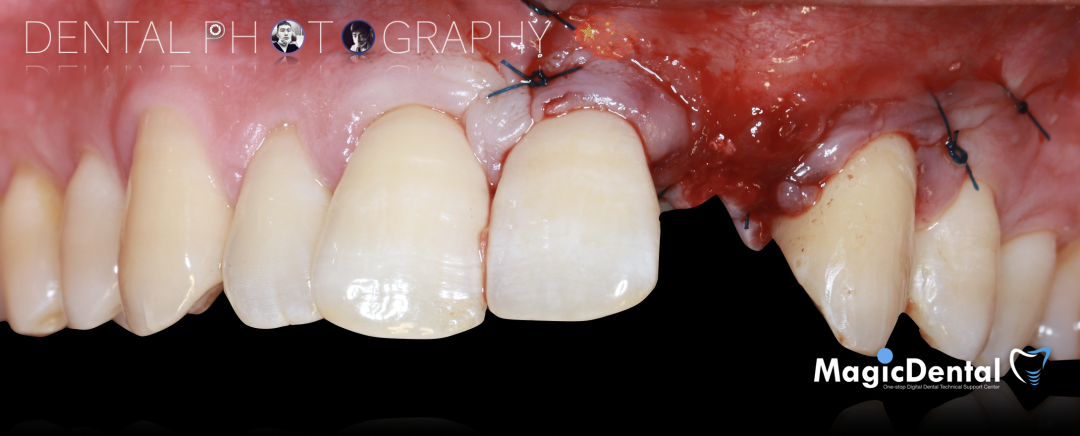

患者术前口内照片

40岁男性患者。

主诉:左上前牙缺失求修复。

现病史:患者因外伤导致前牙松动半年之久,两个月前于外院拔除左上前牙,现自觉不美观来我院就诊。

既往史:既往体健,无其他系统病史,否认重大疾病史,有口腔拔牙史。口腔检查:口腔卫生良好,牙周状况良好,22缺失,缺失间隙约7mm,CT显示缺失牙位置唇颚侧骨壁薄,无对颌伸长,邻牙无移位,上下前牙呈深覆 ,38、48近中阻生。

切开翻瓣,彻底暴露术区,试戴骨块。